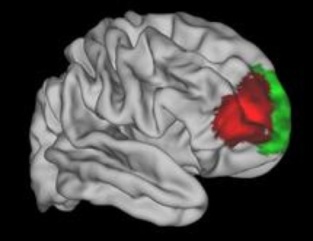

La zona roja parece exclusiva de los humanos. Fuente: Universidad de Oxford.

Los investigadores fueron capaces de comparar las 12 áreas de esa región del cerebro humano con la organización de la corteza prefrontal de mono. En general, eran muy similares, dado que 11 de las 12 áreas se encuentran en ambas especies y están conectadas a otras áreas del cerebro de maneras muy similares.

Sin embargo, un área de la corteza frontal ventrolateral humana no tiene equivalente en el macaco. El autor principal del artículo, Franz- Xaver Neubert, de la Universidad de Oxford, añade: "Esta zona ha sido identificada con la planificación estratégica y la toma de decisiones, así como con la "multi-tarea".

Los investigadores fueron capaces de comparar las 12 áreas de esa región del cerebro humano con la organización de la corteza prefrontal de mono. En general, eran muy similares, dado que 11 de las 12 áreas se encuentran en ambas especies y están conectadas a otras áreas del cerebro de maneras muy similares.

Sin embargo, un área de la corteza frontal ventrolateral humana no tiene equivalente en el macaco. El autor principal del artículo, Franz- Xaver Neubert, de la Universidad de Oxford, añade: "Esta zona ha sido identificada con la planificación estratégica y la toma de decisiones, así como con la "multi-tarea".